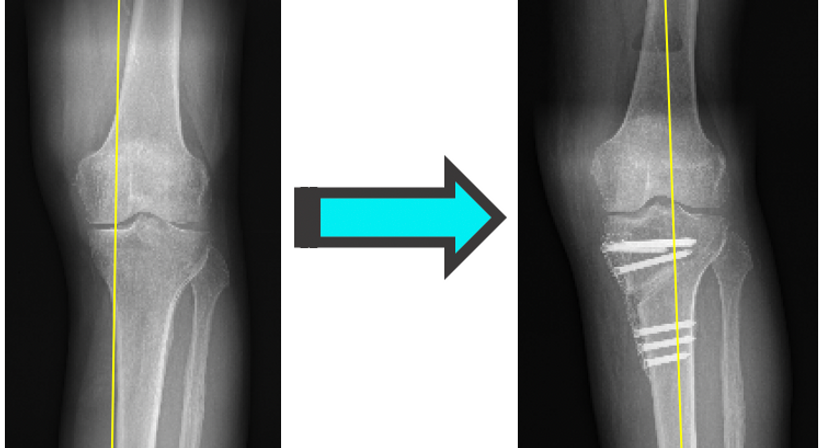

Beinachsenkorrektur / Umstellungsosteotomie

Eine nach innen oder außen gerichtete Fehlstellung der Beinachse wird typischerweise als X- oder O-Beinfehlstellung bezeichnet (Valgusknie bzw-. Varusknie). Eine X- und O-Beinstellung führt u.a. dazu, dass die Gelenkflächen des Knies ungleichmäßig beansprucht werden, wodurch es zu Überlastungsschäden wie Meniskusrissen und Knorpelabnützung kommt.

Insbesondere bei aktiven Patienten ist die Umstellungsosteotomie eine Möglichkeit

Beinachsenfehlstellungen zu korrigieren und somit Folgeschäden, wie z.B. Arthrose, zu vermeiden oder zumindest zu verzögern.

Im Gegensatz zum künstlichen Gelenksersatz (Knieendoprothese) ist die Ausübungen sämtlicher Sportarten nach einer Beinachsenkorrektur erlaubt. Die Korrektur wird meistens im Bereich des Schienbeins, in gewissen Fällen auch am Oberschenkel durchgeführt.

Durch moderne Operationsverfahren mit 3D- Planung und Korrekturschablonen aus dem 3D Drucker, sowie Fixierungstechniken (Plattensysteme) kann das Bein bereits am Folgetag nach einer Umstellungosteotomie wieder belastet werden. Der Krankenhausaufenthalt beträgt in der Regel 2-3 Tage.